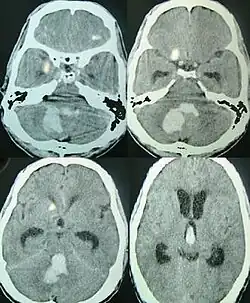

Tanto a angiografia por tomografia computadorizada (ATC) como a angiografia por ressonância magnética (ARM) demonstraram ser efetivas no diagnóstico de malformações vasculares intracranianas após a hemorragia intracerebral.[13] Com tanta frequência, um angiograma de tomografia computadorizada será realizado para excluir uma causa secundária de hemorragia[14] ou para detectar um "sinal local".

A hemorragia intraparenquimatosa pode ser reconhecida na tomografia computadorizada porque o sangue aparece mais brilhante do que outro tecido e é separado da mesa interna do crânio por tecido cerebral. O tecido que envolve um sangramento é muitas vezes menos denso do que o resto do cérebro por causa do edema e, portanto, aparece mais escuro na tomografia computadorizada.[14]